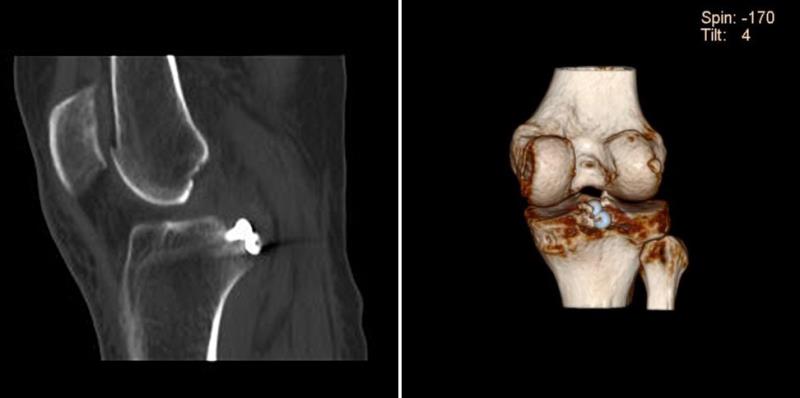

CT提示右膝后交叉韧带胫骨止点撕脱骨折

关节镜下在后交叉韧带胫骨止点撕脱骨折块上植入2枚空心螺钉

术后复查右膝关节CT及三维重建,提示骨折能够达到解剖复位,内固定位置合适